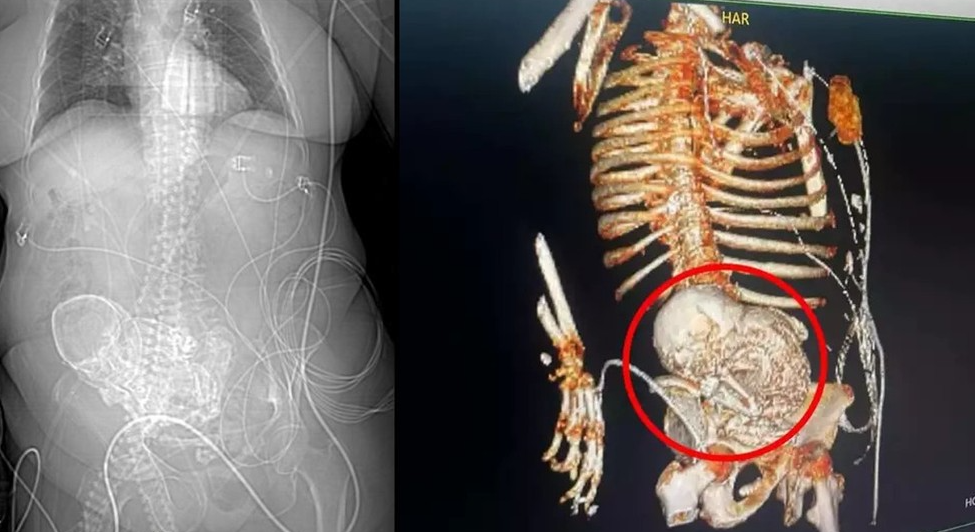

Uma idosa, de 81 anos, descobriu que carregava um 'bebê de pedra', ao ser encaminhada com dores abdominais para o Hospital Regional de Ponta Porã, no Mato Grosso do Sul. A mulher estava com o feto calcificado no abdômen há 56 anos, desde quando ela teve a última gestação.

A mulher deu entrada no hospital com um quadro de infecção grave em 14 de março deste ano. No mesmo dia, uma tomografia constatou o feto calcificado na região do abdômen da idosa. A equipe de obstetrícia da instituição foi acionada e realizou a cirurgia para retirada do feto.